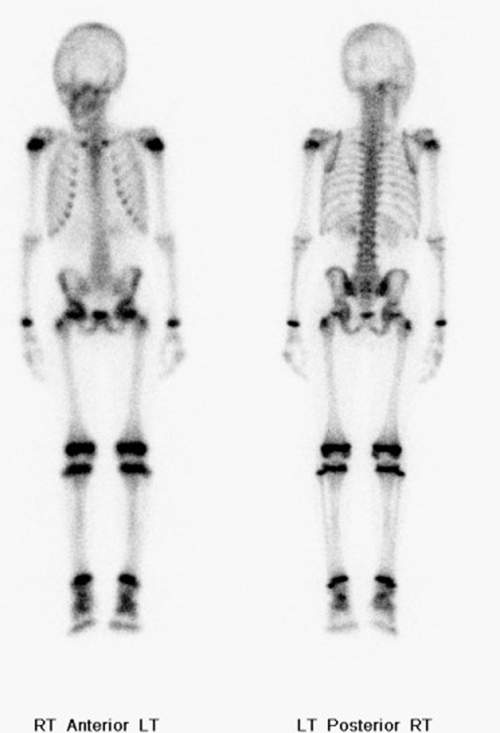

Normal whole body pediatric and adult bone scintigraphy with technetium 99m methylene diphosphonate (MDP) display different features (figure 1). In the pediatric population there is intense radiotracer uptake in the growing physes of long bones. Normal adult whole body planar bone scans with Tc-99m MDP demonstrates normal expected uptake in the bilateral sacroiliac joints, iliac crest, acromioclavicular joints, sternoclavicular joints, and nasal region. Normal radiotracer activity is excreted into the kidneys and urinary bladder.

| Normal pediatric whole body Technetium 99m-methylene diphosphonate (Tc-99m MDP) bone scan displays intense expected radiotracer uptake in the physes of long bones. |